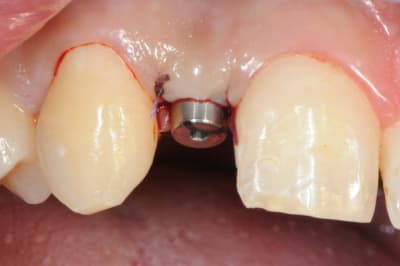

je reviens sur ce cas que j'ai un peu délaissé...

-cicatrisation

-mise en place vis de cica petit diamètre

-ensuite on augmente le diamètre en conservant et en gonflant les tissus gingivaux